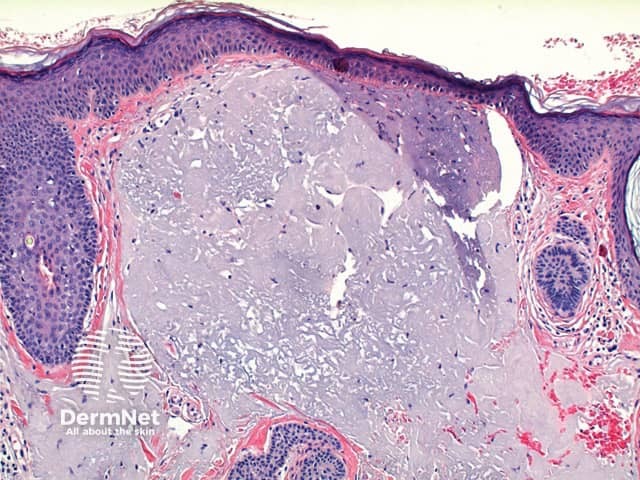

The low power view of Favre-Racouchot syndrome shows multiple comedones, dilated and plugged follicular infundibulae and epidermal cyst formation (Figures 1 and 2). This is set in a grossly solar damaged epidermis, which forms large nodules in the superficial dermis (Figure 3). The comedones are filled with compact keratinous material, while the epidermal cysts contain more loosely arranged laminated keratin (Figures 4 and 5).

Figure 1